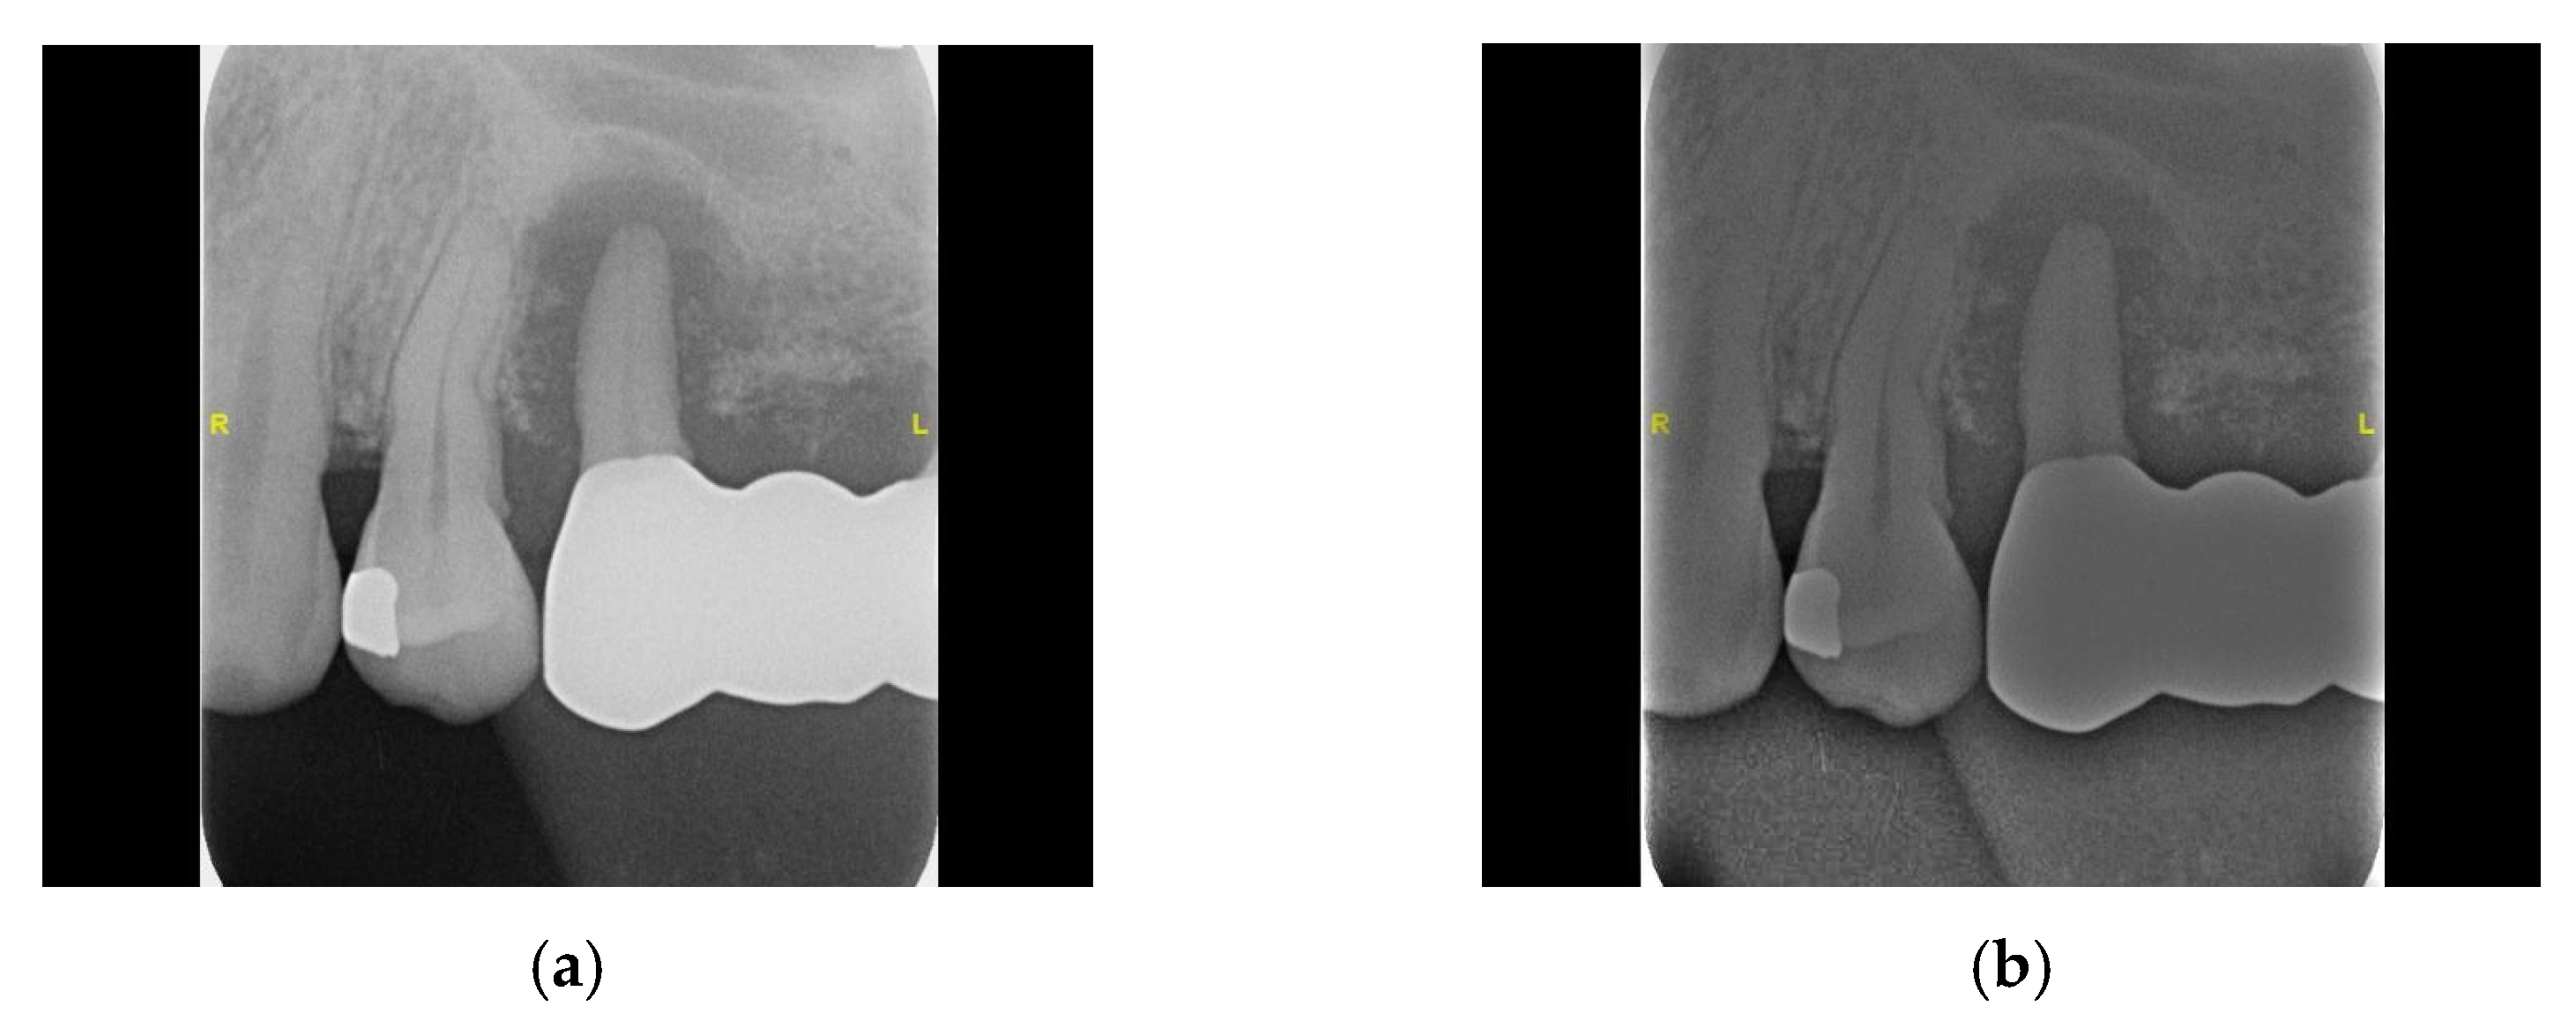

- Aspect 1: Black Padding